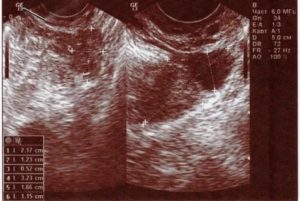

Если месячных нет 1-2 недели и более, при всем при этом вы не исключаете вероятность наступления беременности, наверняка развеять свои сомнения можно сразу несколькими способами. На таком сроке на УЗИ уже видно плодное яйцо (если оно находится в матке).

- Поликистоз яичников. В органе образовываются кисты. Эти образования видны на УЗИ.